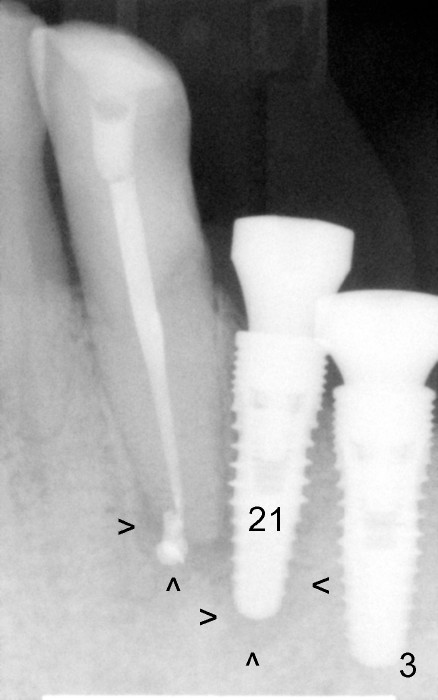

Three weeks post RCT for #22, the patient returns for implant placement at the sites of #19-21 (Fig.1,2). He is asymptomatic. But pain is not well controlled when osteotomy is being done at the site of 21. A shorter and smaller implant (4.1x12 mm, insertion torque <15 Ncm) is placed than planned (4.5x14 mm). One month postop, the implant is not stable at the site of 21 (Fig.3-5). There is a space around the implant, which is continuous with periapical radiolucency (Fig.3 arrowheads). It appears that the immediate implant should have been placed longer following RCT of the neighboring tooth. The tooth #21 has also pre-existing periapical infection.

The patient is scheduled to return 2 months postop. If there is no percussion associated with #22 and the implant at #21 remains unstable, a new PA is to be taken. The implant may be torqued down. If it does not work, the implant is removed. The socket is examined for its integrity. Deepen osteotomy for 1-2 mm and re-place the same implant. If insertion torque is low, use a larger and longer implant.